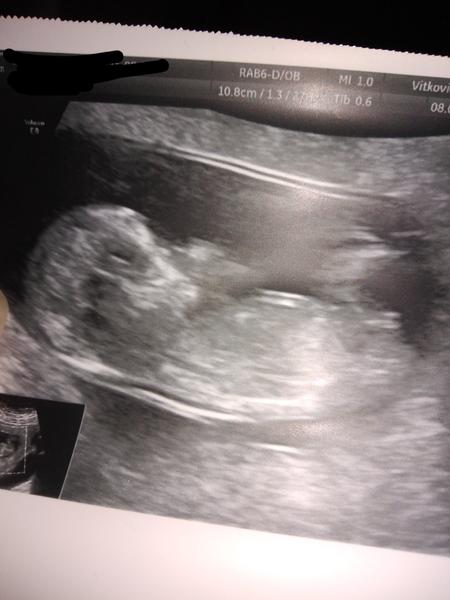

Pohlaví podle hrbolku. Tipl by si někdo?

Ahoj, je tady někdo, kdo by si tipl určit pohlaví podle hrbolku? Vím, že tady takové diskuze již jsou ale jsou staršího roku, takže jsem proto založila novou diskuzi. Snad to nebude vadit. Nejdůležitější je samozřejmě zdravé miminko, jen mě hlodá zvědavost, tím jak sedím doma a nemám do čeho píchnout. 🤷😁😁

Holky a poznáte něco z mé fotky? Doktorka mi neřekla nic 😃 @danzan taky bych tipovala u tebe holčičku 😊

@levandulka_fialova děkuji, mě přišel hrbolek na jednom obrazku vodorovně...ale doktorka aniž by se podívala řekla nevím asi kluk, je to malý tak já nevím a řekla to tak, že to asi ani nebrat vážně 😀😂

@danzan jestli je to fakt hrbolek, tak tipuju... holku😁